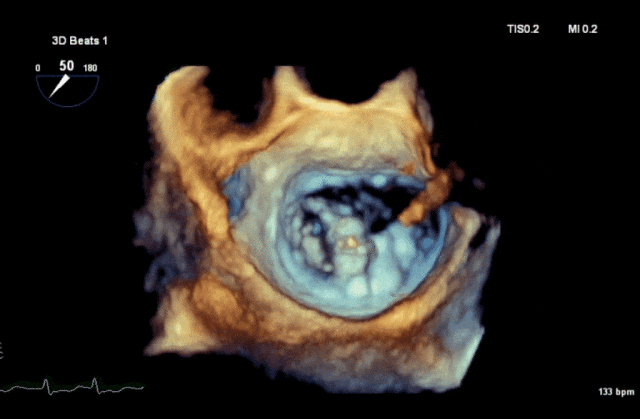

心脏超声示左室增大,二尖瓣2、3区脱垂伴重度反流(腱索断裂),Carpentier分型Ⅱ型,典型Barlow综合征表现;二尖瓣开放面积5.0cm²,3区瓣环内径31mm,前叶长22mm、后叶17mm,前叶收缩期关闭瓣体部分呈拱形突向左房腔,瓣膜游离缘对合欠佳,可见腱索断裂,长度9mm;2区瓣环内径32mm,前叶长22mm、后叶10mm,前后叶均可脱垂;三尖瓣重度反流。CDFI示瓣口重度偏心性反流,反流束沿主动脉后壁走行,肺静脉收缩期可见反向频谱。

术前3D

综合上述术前评估结果,患者二尖瓣、三尖瓣重度反流合并心功能不全,二尖瓣2区、3区瓣叶大面积脱垂,伴腱索断裂,属偏红区Barlow病变。手术团队商讨后一致决定开展经导管二三尖瓣联合钳夹术,优先处理二尖瓣反流,从内到外依次植入2-3枚NeoNova® C6夹合器,在保证瓣口面积的情况下,最大程度夹持瓣叶组织以有效解决反流。术中需注意防止腱索缠绕,有必要可将夹合器延展至“一字型”状态。